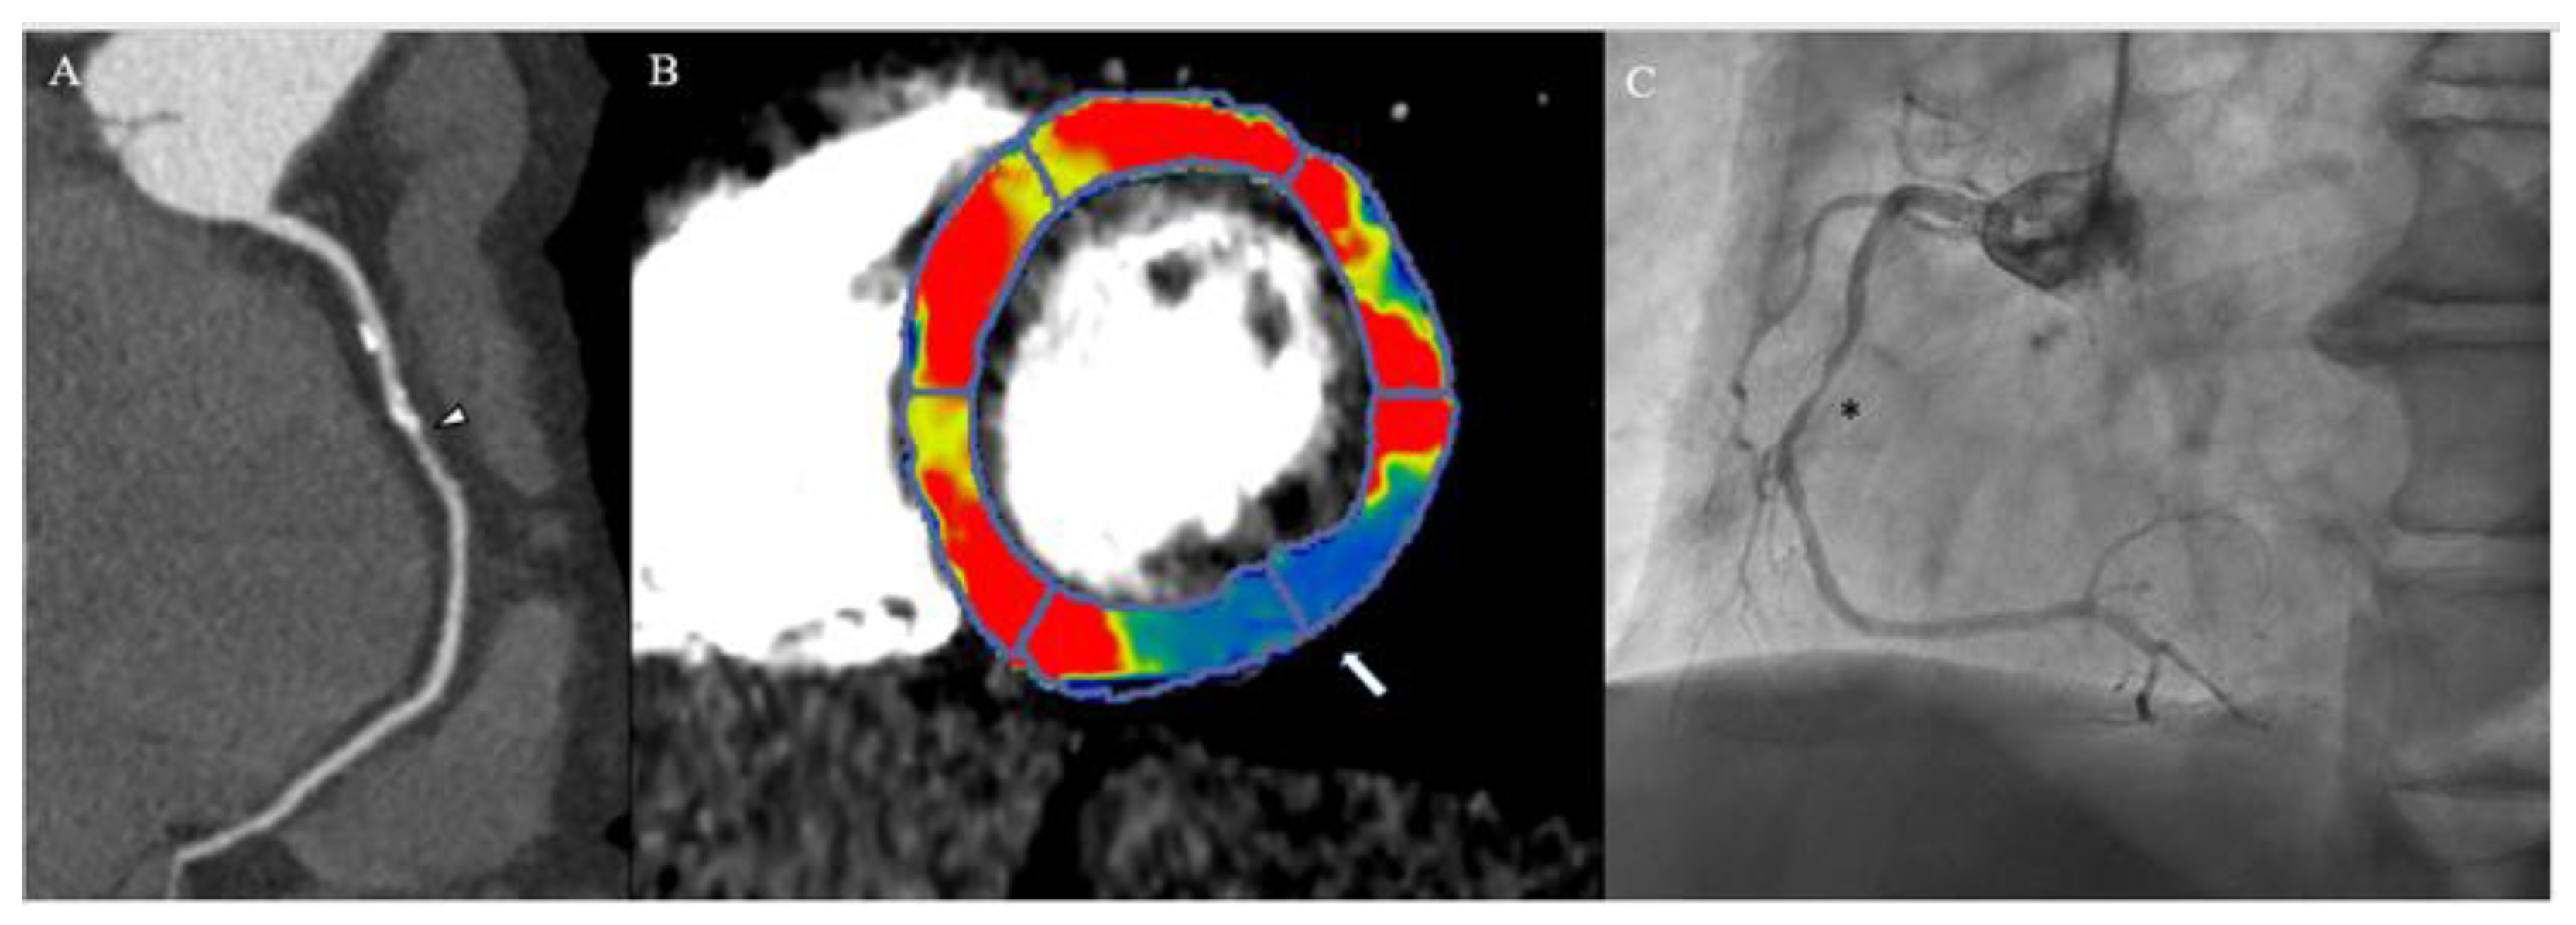

3. Myocardial Computed Tomography Perfusion

3.2. How CTP

3.3. When CTP